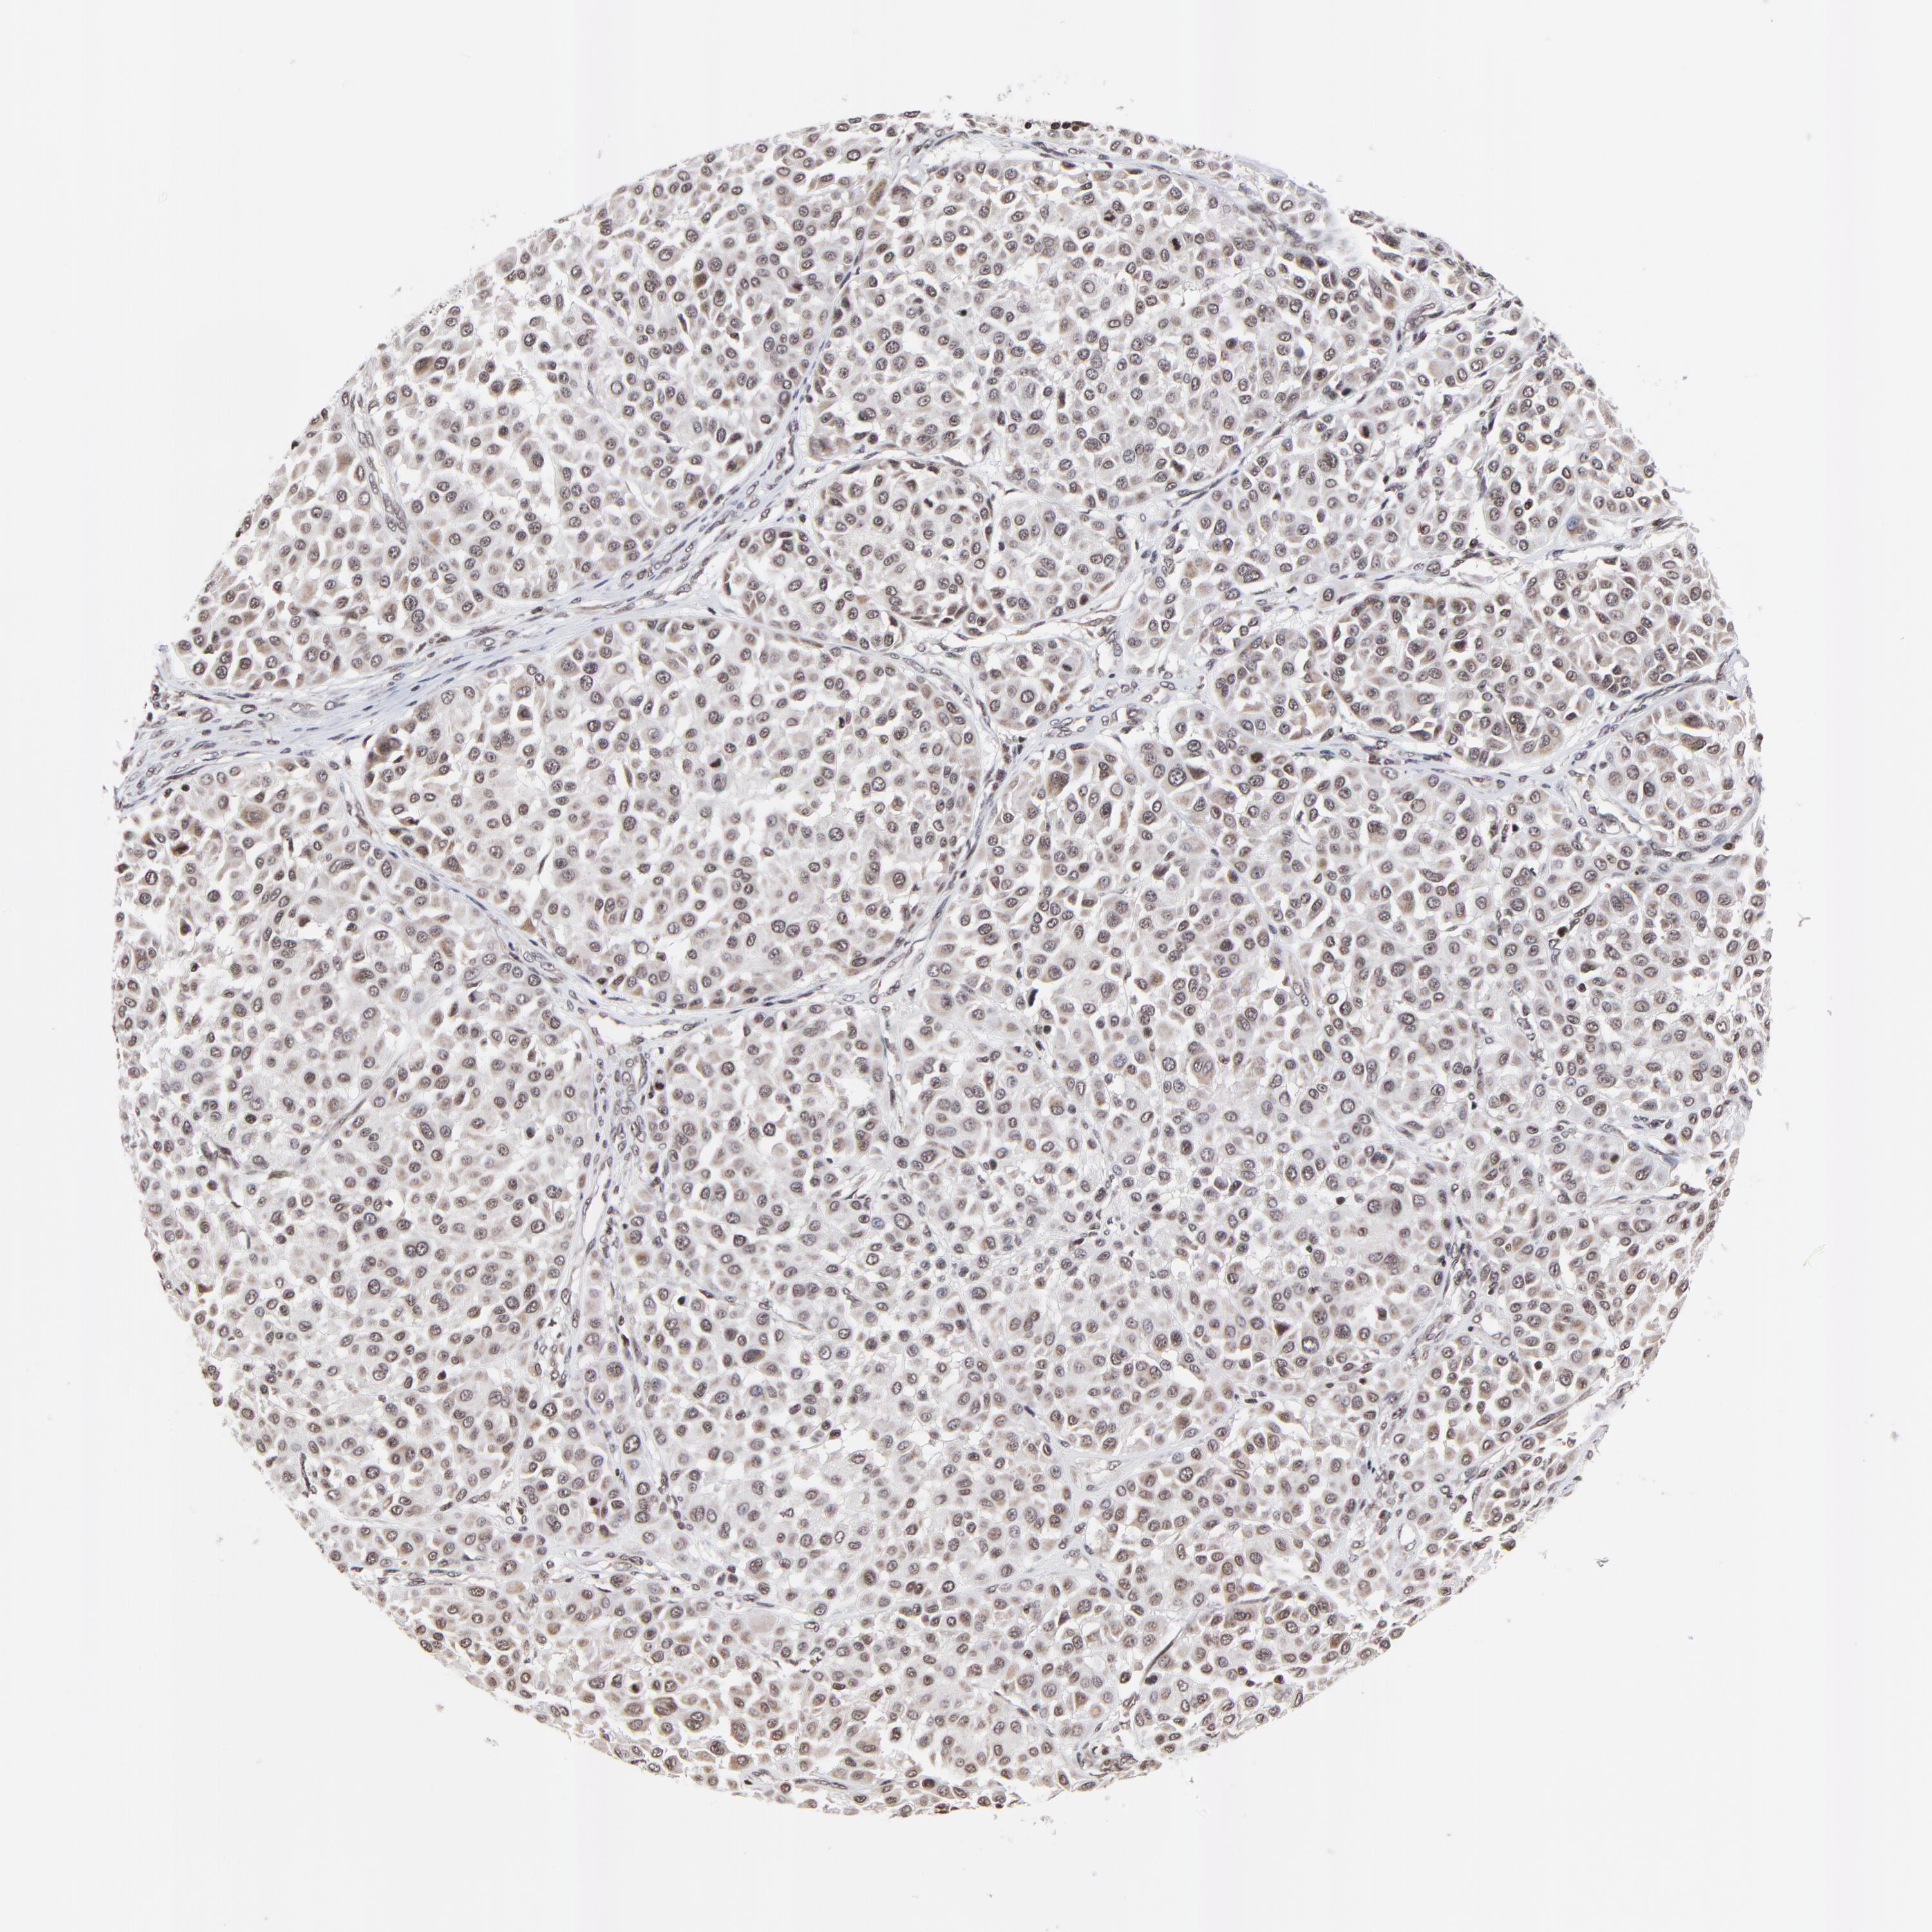

MELANOMA - Protein expressioni

A mouse-over function shows sample information and annotation data. Click on an image to view it in a full screen mode. Samples can be filtered based on level of antibody staining by selecting one or several of the following categories: high, medium, low and not detected. The assay and annotation is described here.

Note that samples used for immunohistochemistry by the Human Protein Atlas do not correspond to samples in the TCGA dataset.

Antibody stainingi

Antibody staining in the annotated cell types in the current human tissue is reported as not detected, low, medium, or high, based on conventional immunohistochemistry profiling in selected tissues. This score is based on the combination of the staining intensity and fraction of stained cells.

Each image is clickable and will lead to virtual microscopy that enables deeper exploration of all samples and also displays staining intensity scores, fraction scores and subcellular localization as well as patient and tissue information for each sample.

Antibody HPA003252

Staining

High

Medium

Low

Not detected

Intensity

Strong

Moderate

Weak

Negative

Quantity

>75%

75%-25%

<25%

None

Location

Nuclear

Cytoplasmic/membranous

Cytoplasmic/membranous,nuclear

Malignant melanoma, NOS

Malignant melanoma, Metastatic site